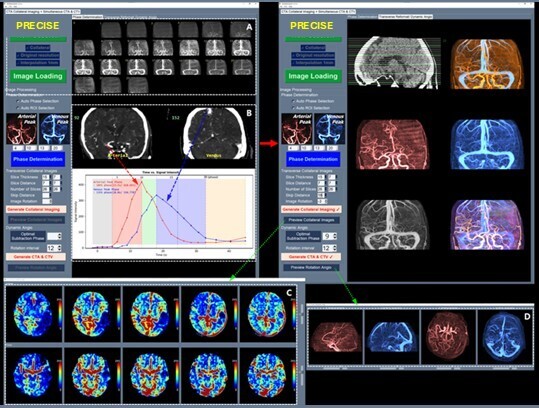

이와 함께 허혈성 뇌혈관 질환 환자를 대상으로 혈관재개통 치료가 필요한 환자 선별을 지원하는 소프트웨어 등 다양한 진단·치료 보조 AI 의료기기들이 혁신의료기기로 지정됐다.